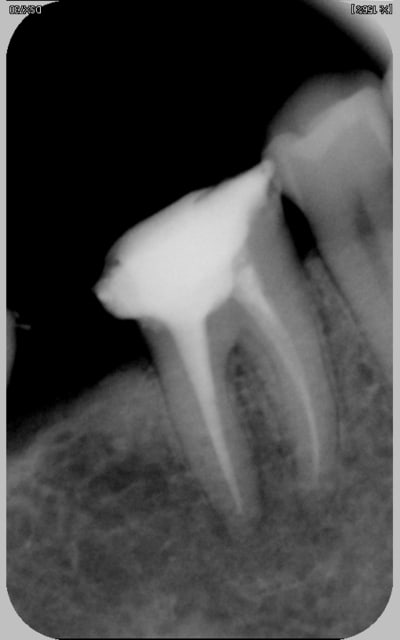

Joli athos. Je me suis souvent demandé pourquoi reprendre tous les canaux quand un seul semble atteint.

Je confirme, jolie provisoire. quand à la radio, c'est la position verticale du capteur (ou du film) sur les molaires qui les inquiète...

ah bon...sais pas pourquoi alors.Les radios sont centrées, même temps minimal d'expo, plans parralléles, sans deformations géométriques (ou deformations proportionnelles), et d'une radio sur l'autre les lectures se reportent...

mais je ne me défends pas, je cherche a savoir:)

en fait pour un rttt, les deux questions que je me posent:

- y a t il pathos? ou risque de pathos.Si oui, j'attaque évidemment.

- sinon, suis je assuré de faire mieux?

Oui, juste qu'il me semble que les dents du secteur molaire/prémolaires devraient être prises avec une radio orientée avec son granbd axe horizontalement...et pas l'inverse comme pour les Incisives et Canines. Bon, je chipote, je te l'accorde. Tant qu'on voit ce que l'on veut finalement... ;-)

PS : En fait, en faisant comme tu fait, tu es obligé de reculer ton capteur par rapport à ta dent (surtout pour les dents sup)...et plus tu t'éloignes, moins ta radio est bonne et précise car la moindre angulation a d'autant plus d'incidence sur les déformations. Je ne sais pas si je suis assez clair. Oui, non ?

je crois...cet axe là?

Je pense, amigo athos!!! (histoire de trouver qquchose :-))))

Quand je parlais de grand axe de la radio, c'est la longueur du capteur qu'il fallait comprendre, pas celui de la dent radiographiée. En gros, pour des molaires/prémolaires, ta radio doit être regardée comme un écran 16/9. Pour les I et C, comme le portarit de la Joconde.

capteur "couché" alors?

dis donc t'es sur que ça va diminuer les déformations ça? enfin bon, je ferai comme ça desormais, mais si je ne vois pas une amélioration merveilleuse de l'image je serai tout déçu déçu déçu...

Bah moi le capteur couché une fois sur deux j'ai pas l'apex. Au moins, debout, j'ai de la marge.

oui, mais aussi je ne suis pas persuadé que dans le cas ou on veut faire une correction parallectique (heu...pas sûr de l'orthographe du terme, mais = cale, faisceau déporté et deformations proportionnelles) raccourcir la longueur du capteur ne complique pas la chose

Bon, je vais essayer d'être plus clair :

Pourquoi les bite-wings permettent-ils d'avoir une meilleure définition des caries interproximales débutantes ? Parce que le film ou le capteur est collé aux dents. Plus la distance film/capteur - dents radiographiées augmente, plus la moindre inclinaison (que ce soit dans le sens horizontal ou vertical) aura une incidence sur l'image obtenue sur le film. A l'inverse, plus le film est proche des dents, moins il y aura de déformations dues à un parallèlisme imparfait.

Dans le cas de la prise d'une radio sur des dents maxillaires, si tu mets ton capteur en position verticale, tu es obligé de la reculé pratiquement au niveau du raphé médian pour qu'il soit bien parallèle à l'axe des dents. De plus, du fait de la longueur du capteur, il y a peu de chances que tu puisses faire mordre ton patient sur la partie plastique des deux côtés (sup et inf) en même temps, résultat le porte capteur est en équilibre précaire ce qui n'améliore pas la satbilité de l'ensemble pendant la prise cliché.

ps: je t'ai dit que je tenais le capteur avec mes doigts (ééhhhh oui...je sais) plaqué contre la dent, plus près et plus parrallele on peut pas, le generateur est a anode déportée, je n'utilise pas de viseur mais je m'applique a ce que le faisceau soit bien perpendiculaire au plan et centré sur le milieu de....l'objet ou le capteur? hmmm?...